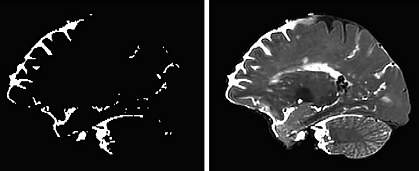

One volunteer underwent MRI using a technology called T2/FLAIR at 12 and 24 hours after surgery, and the other 4 underwent T2/FLAIR imaging at 24 and 48 hours after surgery.

The scans showed cerebrospinal fluid flowing into the brain through distinct channels—along the perivascular spaces, the fluid-filled spaces that run alongside blood vessels in the brain. These findings match earlier imaging results seen in mice. Dye could also be seen moving from these spaces into the functional tissue of the brain.